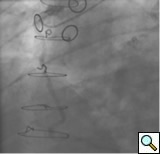

The most commonly used catheters for left heart catheterization and vein graft angiography can be seen in Figure 1 and Figure 4-13. Most of the vein grafts have horizontal take off and can be successfully engaged using a commonly used Judkins right number 4 (JR4) catheter. The JR4 catheter is the most commonly used catheter for the engagement of the right coronary ostium with horizontal take off. However, many vein grafts have unusual take off requiring different catheters. Many right coronary vein grafts have steep inferior take off making the ostial engagement with JR4 difficult or impossible (Figure 10). In such a scenario, a multipurpose catheter which has a shallow angulation is the best choice (Figure 11). The second major challenge in engaging vein graft ostia, particularly vein grafts supplying the left coronary arteries, is the shape of the aorta. A large aorta can make it very difficult for the JR4 catheter to reach the ostial vein grafts. In such a situation, Amplatz (AR) right and left (AL) catheters can be very helpful to reach the vein graft ostia. Amplatz catheters have a larger primary curve and have been used successfully in unusual superior take off of left coronary arteries or vein grafts and in large aorta. Amplatz catheters are available in different sizes (from smaller to larger curve: AR 1, AR2, AL2, AL2 and AL3). Occasionally, a very superior take off of a vein graft requires specially designed bypass graft catheters. Amplatz catheters are also extremely helpful in engaging native right coronary ostium with anterior take off.

PCI of the vein and arterial grafts have unique challenges. For any PCI, guide support is very important for successful balloon and stent delivery. In a tortuous vein graft with a steep angle, advancement of a stent can be very difficult and challenging. Therefore, it is important to choose the best available catheter before starting PCI. Similar to the right coronary angiography, a JR4 guide catheter is most commonly used in this setting. However, Amplatz guide catheters for left vein grafts and multipurpose catheters for right vein grafts are better choices in certain anatomy. In Figure 8 and Figure 10 two examples of poor guide support in two vein graft interventions can be seen. Initially, a JR4 guide was used for PCI of the vein graft supplying the left anterior descending artery (LAD) without any success. However, after changing the guide to an Amplatz left 2 guide catheter, we achieved excellent support without any difficulty in advancing two stents (Figure 9). In Figure 10, difficulty is illustrated in engaging the vein graft ostium supplying the right coronary artery with a JR4 catheter. This vein graft has a very steep inferior take off from the aorta. After changing the guide to a multipurpose catheter, we were able to deliver three stents successfully without any difficulties (Figure 11). Similar challenges exist in the treatment of the left IMA or right IMA. These arterial grafts can be extremely tortuous making stent delivery very difficult. It may be necessary to use short length stents for a better deliverability or stents with lowest profile. Usually, similar to the native coronary intervention, a 6 French guide is appropriate for the routine use.